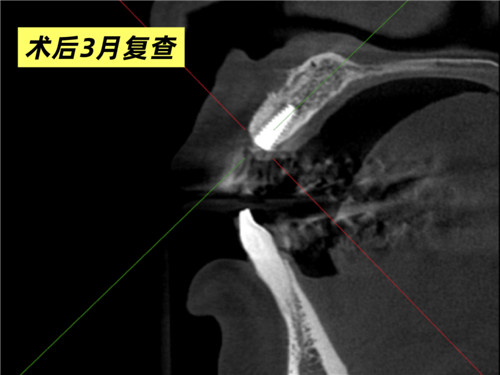

口腔科主任牛躍、副主任醫(yī)師鮑磊接診后,為其完善術(shù)前CBCT(口腔頜面錐形束CT)檢查,細(xì)致評(píng)估口腔條件,發(fā)現(xiàn)患者牙槽骨吸收嚴(yán)重,骨厚度僅4mm,術(shù)中需要植入人工骨粉。在征得患者同意后,科室團(tuán)隊(duì)精準(zhǔn)操作,術(shù)中植入骨粉并覆蓋骨膜,僅用30分鐘便成功完成手術(shù)。3個(gè)月后復(fù)查CBCT,植體與周圍骨質(zhì)結(jié)合良好,科室團(tuán)隊(duì)行牙冠修復(fù)后,患者對(duì)最終效果非常滿意,重新綻放自信笑容。